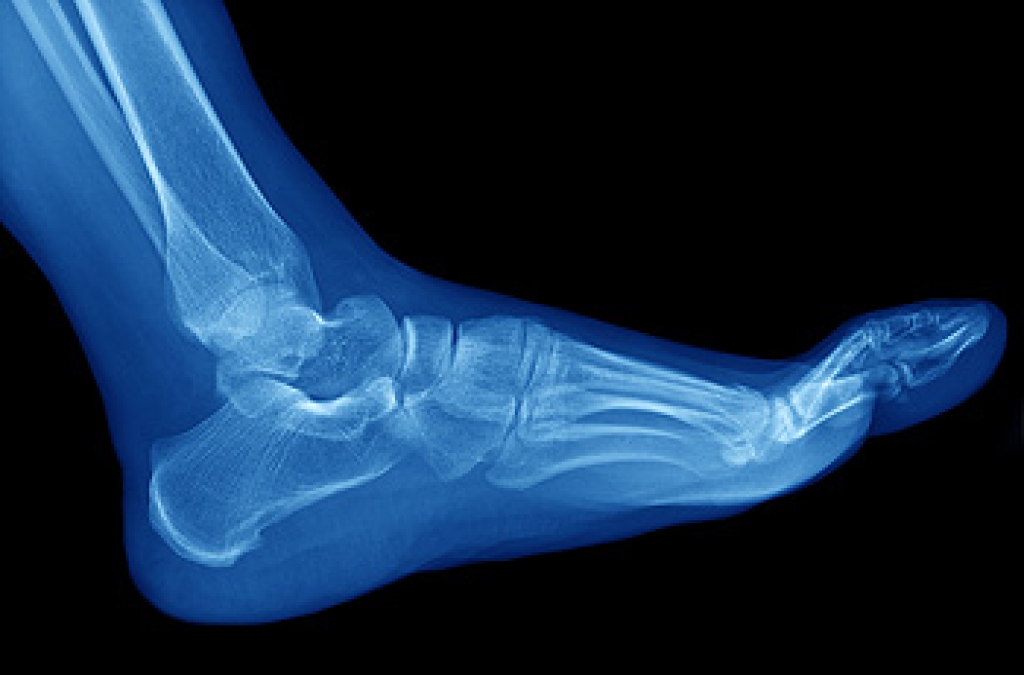

Stress fractures develop when a bone that’s constantly under stress eventually weakens. It typically occurs on the outside of the bone and happens due to repetitive motion. Many professional athletes and runners develop this condition, as overuse of the bones in the foot is common. The way the foot is structured may be another cause, as having flat feet or higher arches may be a contributing factor in developing stress fractures. When overdoing a specific activity, the risk is high for developing these fractures. There may not be physical signs and symptoms from the fracture, but when the activity resumes, pain is often felt. An x-ray is used to determine exactly where the fracture is. Recovery comes from resting the foot and being careful not to put stress on the bones. Occasionally a medical boot is worn to keep the fracture from worsening, in addition to engaging in physical therapy. Please seek the advice of a podiatrist if you feel you have a stress fracture in the foot or ankle.

Stress fractures occur in the foot and ankle when muscles in these areas weaken from too much or too little use.  The feet and ankles then lose support when walking or running from the impact of the ground. Since there is no protection, the bones receive the full impact of each step. Stress on the feet can cause cracks to form in the bones, thus creating stress fractures.